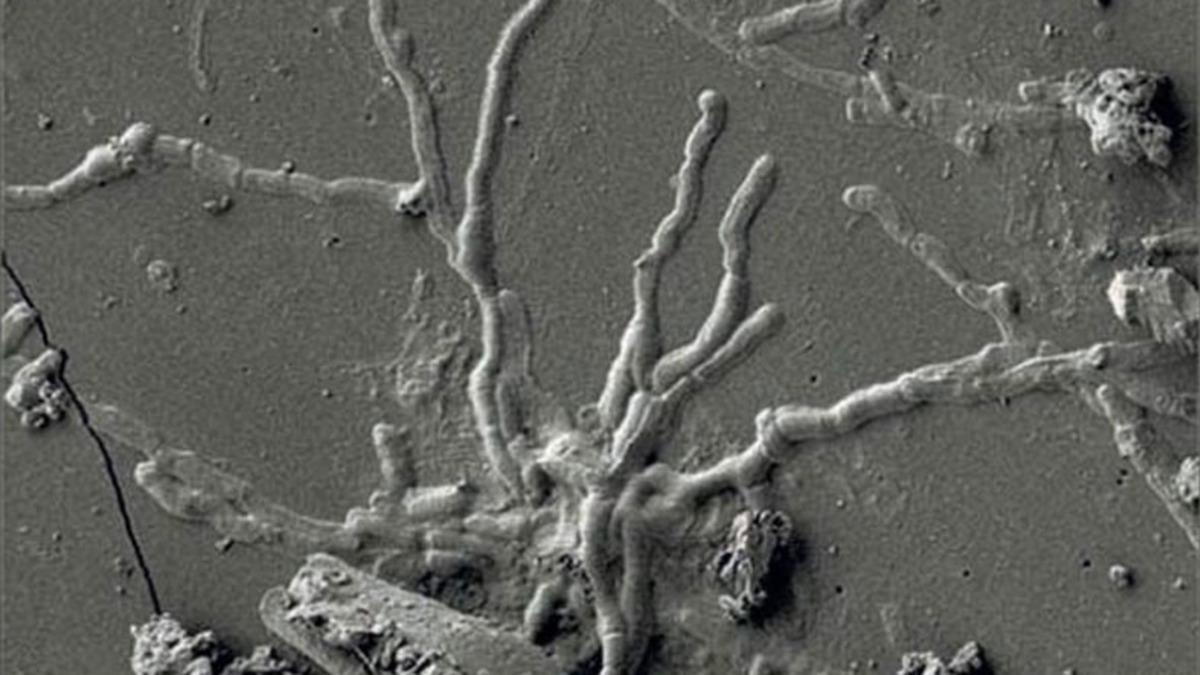

İki bin yıla rağmen sağlam kalmayı başardılar:

Araştırma ekibinin başındaki isim olan Napoli II. Federico Üniversitesi'nden adli antropolog Pier Paolo Petrone, yüzüstü yatan iskeletin yakınında çalışma yaparken iskeletin 'kafatasının içinde parıldayan cam gibi bir şey' gördüğünü belirtti. Yapılan çalışmalar sonucunda bu parlaklığın ne olduğu anlaşıldı.

Petrone ve meslektaşları, kafatasının içinde gördükleri bu parlak malzemenin ölen kişinin yoğun ısı nedeniyle git gide cama dönüşerek bozulmadan korunan beyindeki sağlam beyin hücreleri olduğunu keşfettiklerini açıkladı. Yani kafatasının içindeki beyin hücresi, yanardağın patlamasının ardından geçen iki bin yıla rağmen sağlam bir şekilde duruyordu.

Petrone, kişinin beyin hücrelerinde yaşanan bu durumun nedenini de açıkladı. Petrone'nin açıklamalarına göre beyin, sıcak volkanik küle maruz kaldıktan sonra sıvılaşmış ve ardından volkanik kül yatağının hızla soğumasıyla hemen camsı bir malzemeye dönüşmüş olmalıydı.

İskelette yapılan keşifler yalnızca bununla da sınırlı değildi. Araştırmacılar, aynı iskelette beyin gibi cam hale gelmiş olan omurilikte de sağlam şekilde duran sinir hücreleri keşfetti. Tüm bu keşifler, bu tarz bir örnek ne antik kentte ne de başka bir yerde bulunamayacağından bilim dünyası için büyük bir önem taşıyor.